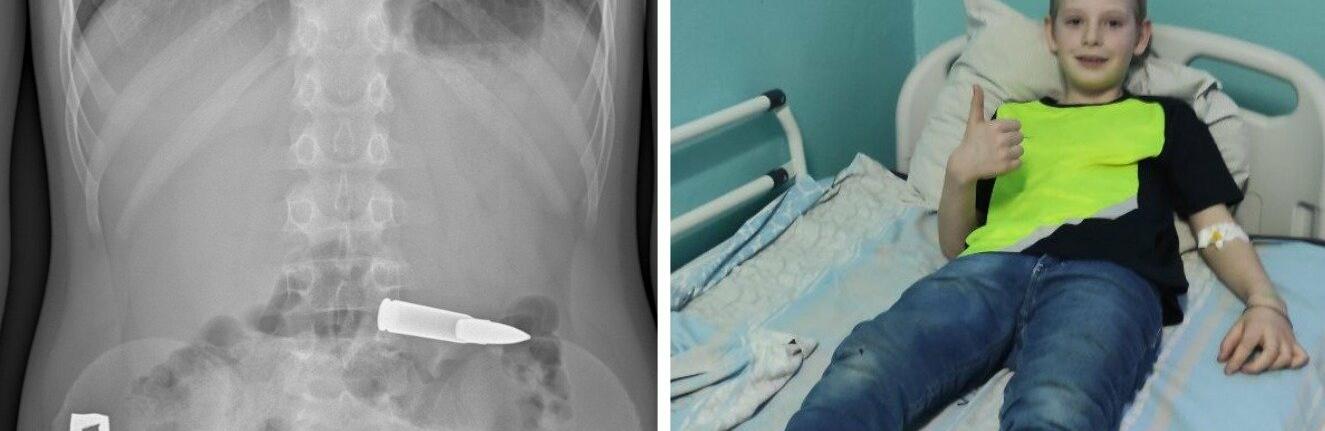

Дівчина проковтнула 20-сантиметрову зубну щітку, намагаючись "врятуватися" від їжі: ідея закінчилася плачевно

Зубна щітка зненацька побувала всередині 21-річної дівчини через її неакуратні дії znaj.ua »